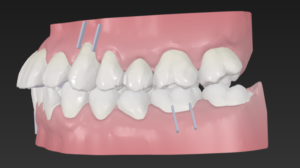

この歯並びの治し方は

歯と歯の間を少し削りスキマを作り

歯をキレイに整列

この時

上の歯は少し多めに歯と歯の間を削り

でっ歯を改善

患者様は気づいていませんが

実は上下の正中は大きくズレていて

これを片側にⅢ級ゴムを装置して矯正